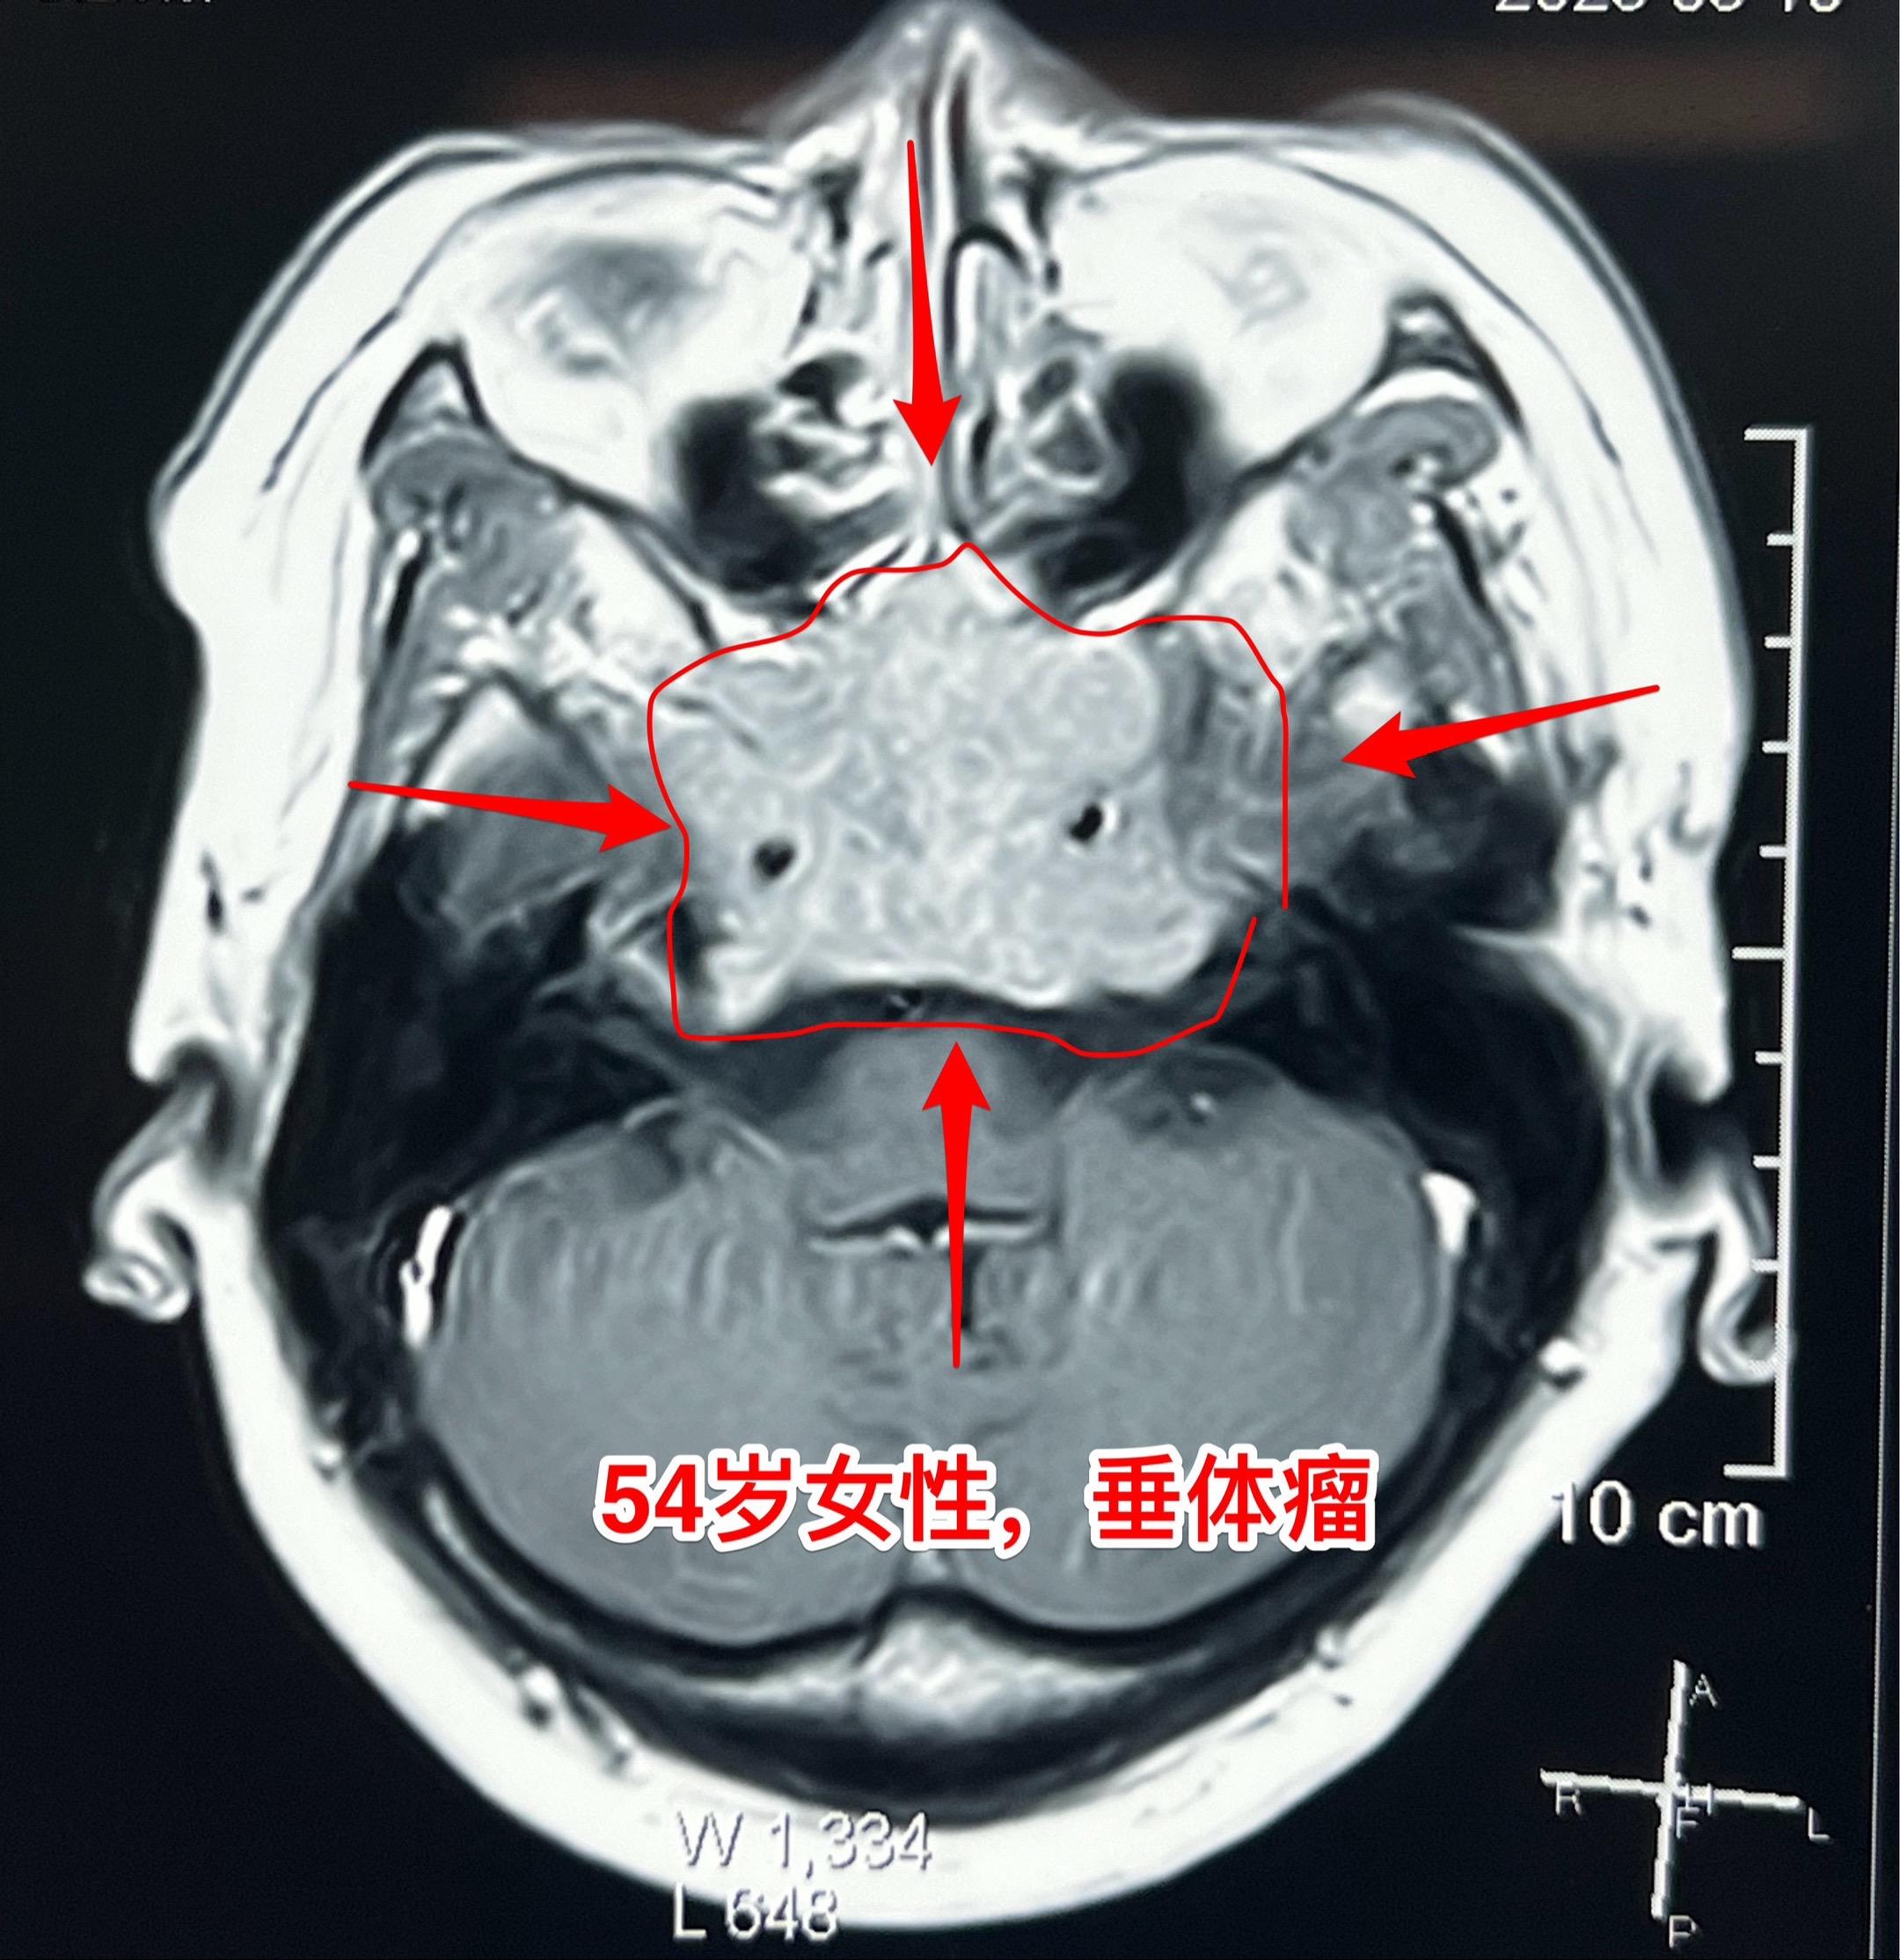

侵袭性垂体瘤第二次手术。54岁女性,2023年9月因垂体瘤作了第一次手术,是开颅手术,当时左眼视力下降。把颅内的肿瘤切除了,蝶窦内、海绵窦内的肿瘤没有动,计划二期手术。 2025年5月病人感觉左眼视力又有下降,来作第二次手术,磁共振、CT显示肿瘤巨大,是典型的侵袭性垂体瘤。这次只能采用经鼻手术了。昨天顺利完成手术。 今天病人没有出现脑脊液鼻漏症状,自感很轻松,精神好。